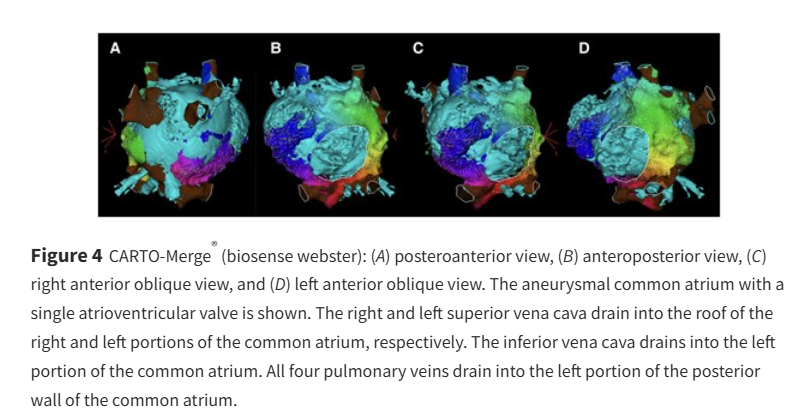

Find out how catheter ablation of atrial flutter was performed in a univentricular heart, common atrium & single AV valve ow.ly/VvB950VOPeG #EHJCaseReports Philipp Sommer Tee Joo YEO Aaysha Cader Boldizsar Kovacs Erik Rafflenbeul A.Nazmi Calik Obayda Azizy Sara Moscatelli EHJCaseReports Editor-in-Chief